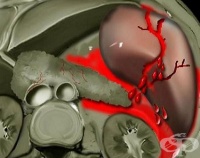

S36.1 Травма на черния дроб или на жлъчния мехур

Черният дроб като паренхнмен - орган е един от най-често засегнатите в корема органи при травми. Бър...